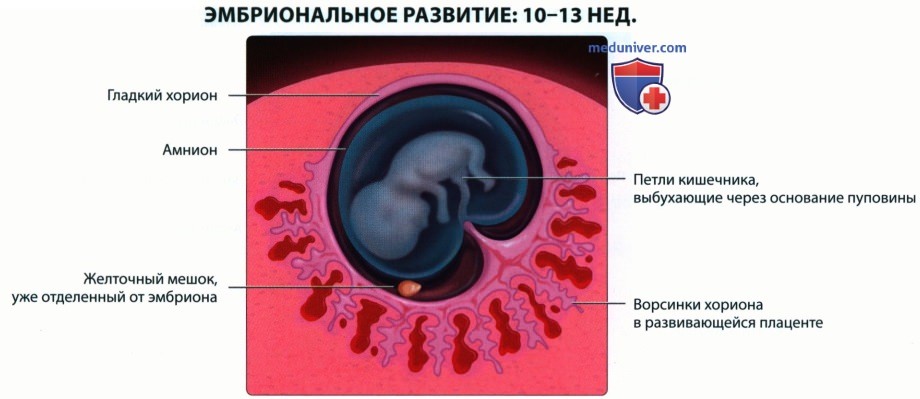

Формирование Плода в Первом Триместре: Важные Этапы